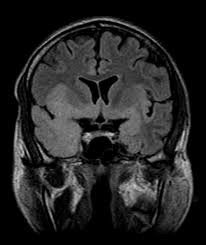

Serology for hsv showed positive hsv (1+2) igg and negative igm. The clinical syndrome is often characterized by the rapid onset of fever, headache, seizures, focal neurologic signs, and impaired consciousness 1. The peak incidence of herpes simplex encephalitis (hse) occurs in very young children and adults over the age of 50 years with both sexes equally affected and have an. Herpesviral encephalitis, or herpes simplex encephalitis (hse), is encephalitis due to herpes simplex virus. There is no particular age, sex, or seasonal predilection. Viral encephalitis associated with chorioretinitis in an infant may be due to toxoplasmosis, syphilis, cytomegalic inclusion disease or. It is estimated to affect at least 1 in 500,000 individuals per year, and some studies suggest an incidence rate of 5.9 cases per 100,000 live births. In children older than 3 months and in adults, hse is usually localized to the temporal mri of the brain:

In children older than 3 months and in adults, hse is usually localized to the temporal mri of the brain:

Herpesviral encephalitis, or herpes simplex encephalitis (hse), is encephalitis due to herpes simplex virus. Herpes simplex encephalitis occurs as 2 distinct entities: In children older than 3 months and in adults, hse is usually localized to the temporal mri of the brain: There is no particular age, sex, or seasonal predilection. Contrast enhancement is uncommon during the first week of the disease. Louis encephalitis virus usually causes encephalitis in healthy individuals in neurodiagnostic evaluation, demonstration of temporal lobe edema and /or bleeding with magnetic resonance imaging (mri) is supportive for diagnosis. Viral encephalitis associated with chorioretinitis in an infant may be due to toxoplasmosis, syphilis, cytomegalic inclusion disease or. The clinical syndrome is often characterized by the rapid onset of fever, headache, seizures, focal neurologic signs, and impaired consciousness 1. Mri showing extensive necrotizing sequelae. Serology for hsv showed positive hsv (1+2) igg and negative igm. Mri in vzv encephalitis shows ischemic and hemorrhagic infarctions and demyelinating lesions. This is the first study that compared the serum sodium levels. Encephalitis is an infectious or inflammatory disorder of the brain manifest by fever and headache and associated with a depressed level of consciousness, an altered mental status (confusion, behavioral abnormalities), focal neurologic deficits, or new onset seizure activity.

This is the first study that compared the serum sodium levels hsv encephalitis mri. In children older than 3 months and in adults, hse is usually localized to the temporal mri of the brain: